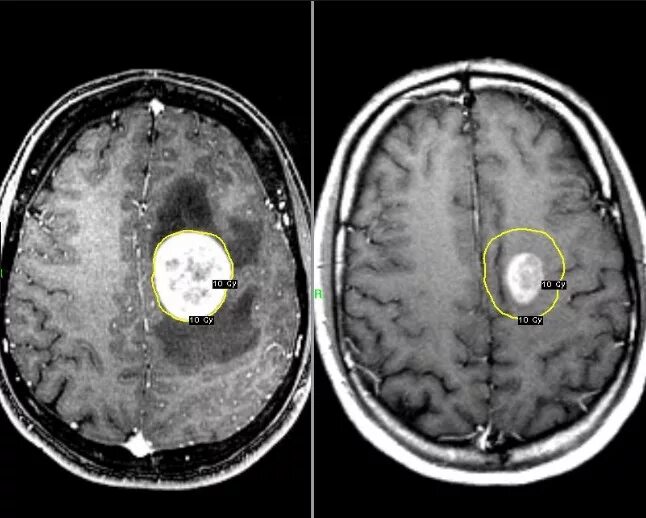

Метастазы головного мозга кт